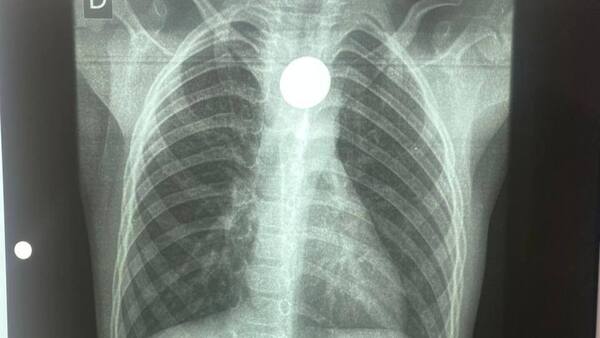

Carlos Morínigo se ofrece a capacitar al personal de blanco del Chaco tras caso de niño con moneda atascada

Un nuevo caso de emergencia pediátrica en el interior del país volvió a poner de manifiesto la necesidad de descentralizar la atención médica especializada, ante lo cual el doctor Carlos Morínigo se ofreció a capacitar al personal de blanco. ...[Leer más]